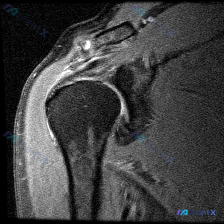

这是一张肩关节冠状位T2序列MRI,扫描范围覆盖肩峰、肩锁关节、冈上肌肌腱、肱骨头、肩关节间隙和三角肌,我们先明确正常信号基准:T2序列正常肌腱是低信号(黑色),关节液、水肿是高信号(亮白色),肌肉是中等偏低信号。

- 冈上肌肌腱远端附着区:可见明显的线状高信号影,直接穿透了肌腱全层厚度,原本正常的低信号紧密结构连续性中断,符合全层撕裂的表现

- 肩峰下-三角肌下滑囊:滑囊内有明显的高信号积液,这是因为关节液通过肌腱撕裂口流进了滑囊,继发引起滑囊炎

- 盂肱关节腔:只有少量高信号液体,属于正常或轻微积液,没有太大诊断意义

- 肩峰下间隙:可以看到肌腱撕裂后断端回缩,肩峰下间隙已经和关节腔形成了沟通